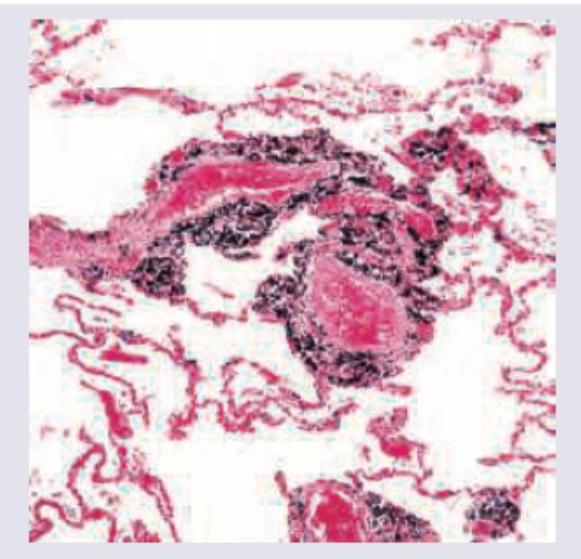

A 25-year-old woman with ocular myasthenia Gravis on prednisolone for last 5 years is having cough with night sweats and significant weight loss. The lung histopathological specimen shows:

Explanation: ***Pneumocystis carinii*** - The patient is on chronic **prednisolone** (a corticosteroid), which causes **immunosuppression**, making her susceptible to opportunistic infections like *Pneumocystis jirovecii* pneumonia (PJP), formerly known as *Pneumocystis carinii* [1]. - Symptoms like **cough, night sweats, and significant weight loss** are consistent with a chronic opportunistic infection in an immunocompromised host [1]. *TB* - While **TB** can cause cough, night sweats, and weight loss, it is less likely to be the primary diagnosis in a patient on chronic corticosteroids without other specific risk factors for TB exposure. - Histopathology for TB would typically show **granulomas with caseous necrosis**, which is not the most common opportunistic infection in this scenario. *Aspergillosis* - **Aspergillosis** can occur in immunocompromised patients [1], but it often presents with specific features like **hemoptysis** or **fungal balls** (aspergilloma) in the lungs. - Histopathology would show **septate hyphae with acute angle branching**, which is distinct from *Pneumocystis*. *Mucormycosis* - **Mucormycosis** is a severe fungal infection typically seen in patients with **diabetes mellitus** or profound immunosuppression, often affecting the sinuses and brain. - Lung involvement is possible but less common than PJP in this clinical context, and histopathology would show **broad, non-septate hyphae with right-angle branching**. **References:** [1] Cross SS. Underwood's Pathology: A Clinical Approach. 6th ed. Common Clinical Problems From Respiratory Tract Disease, pp. 318-319.